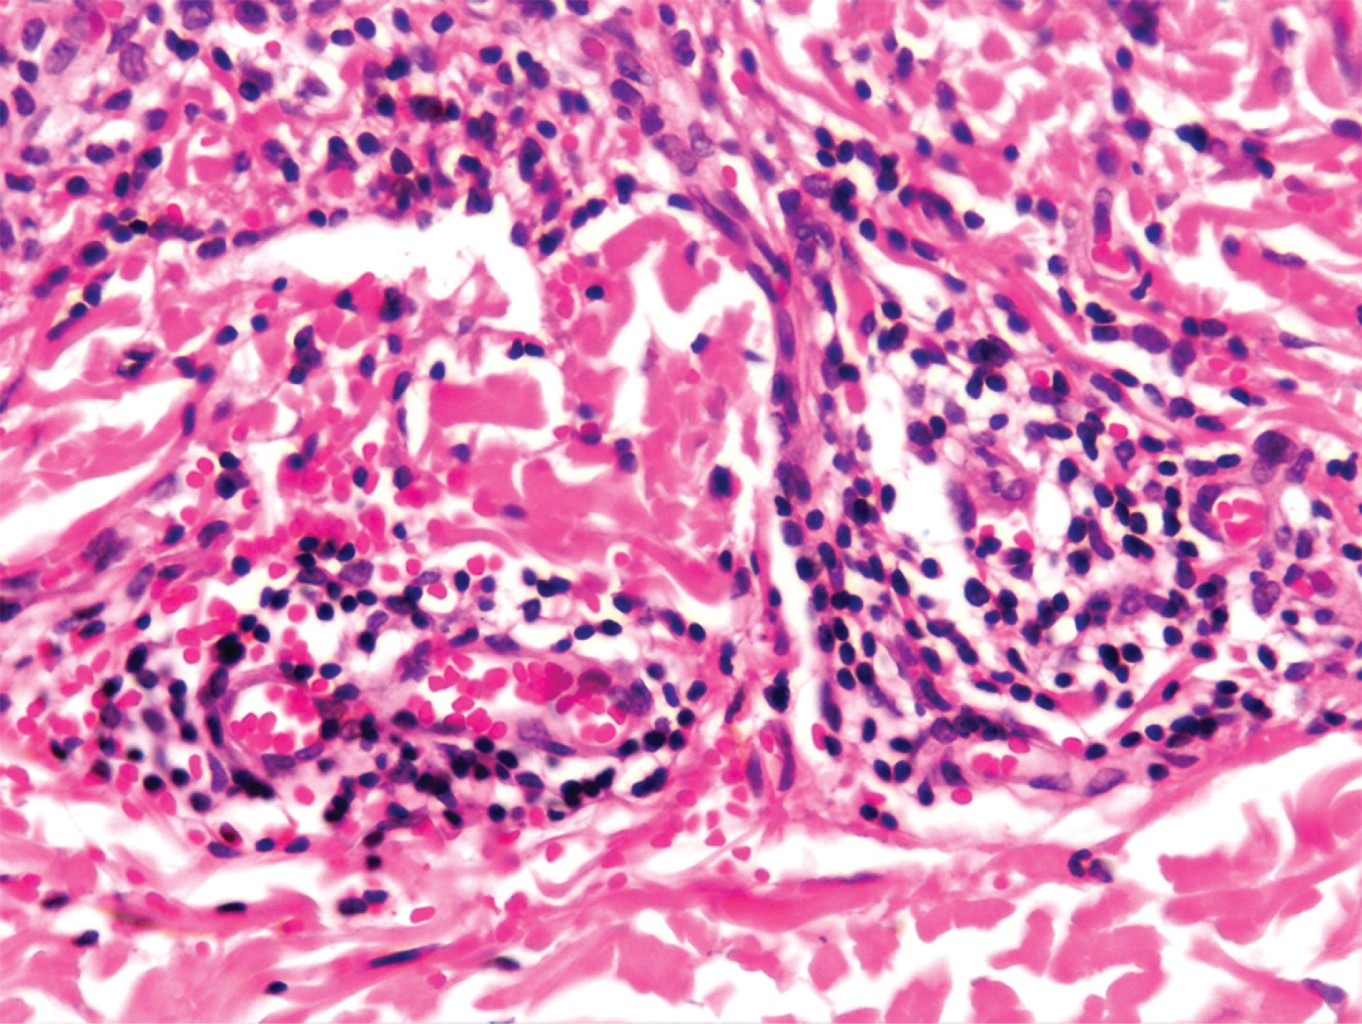

Las imágenes histopatológicas muestran cortes constituidos por múltiples vasos de pequeño calibre de paredes delgadas, dilatados, congestionados, ubicados en la dermis superficial, media, y en menor cantidad en la dermis profunda. No se observan datos de neoangiogénesis.1,7,10

Con el diagnóstico clínico presuntivo de telangiectasia nevoide unilateral versus angioma serpiginoso, se realizó una biopsia incisional de una de las lesiones del hombro. El estudio histopatológico describe una epidermis con escasa capa córnea, aplanamiento de los procesos interpapilares e hiperpigmentación de la capa basal. En dermis superficial se observan vasos dilatados y congestionados, rodeados por infiltrados moderadamente densos, constituidos por linfocitos e histiocitos, además de algunas zonas con extravasación de eritrocitos; resto del corte sin alteraciones (Figuras 4 y 5). Con esto se realiza un diagnóstico histopatológico de dermatitis perivascular superficial con extravasación de eritrocitos, y al realizar correlación clínico-histopatológica se concluye que se trata de un caso de telangiectasia nevoide unilateral adquirida (TNUA). Se solicitan estudios de laboratorio para completar el abordaje (biometría hemática, química sanguínea, perfil de hepatitis viral, prueba de embarazo), todos ellos con resultados dentro de parámetros normales. Se explica ampliamente a la paciente la naturaleza y evolución de su padecimiento. Al ser el dispositivo intrauterino liberador de levonorgestrel el único factor hormonal identificado en la paciente, se sugiere que, en conjunto con el Servicio de Ginecología, se considere cambiar el método de planificación familiar por uno no hormonal. Se da tratamiento con medidas generales.